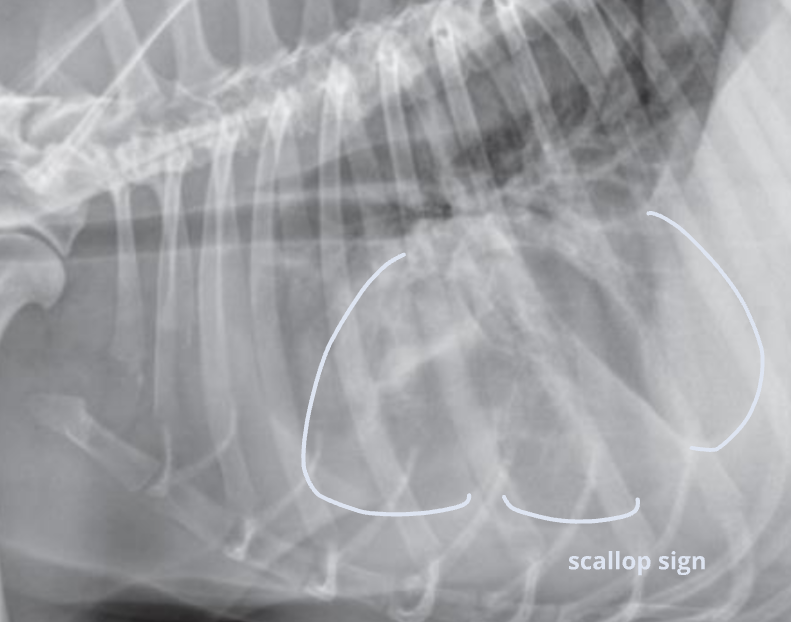

Radiographic signs

심장이 떠 있고, 폐가 쪼그라듦

- Interlobar fissure widening

- Lung retraction

- Pleural wall thickening

- Scallop sign

- Cardiac effacement

- Blunt angle

- Retraction of pleural surface

- Collapsed lung (→ opacity 증가)